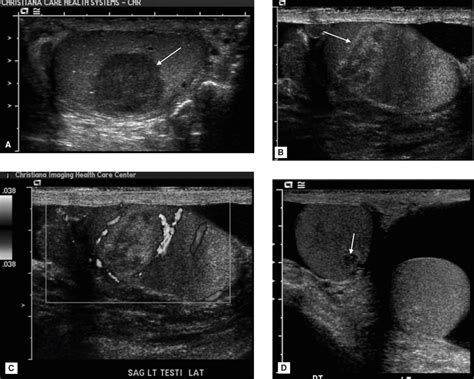

When you visit a doctor for a cyst on scrotum, they will perform a physical examination to feel the size, texture, and location of the lump. They may use a technique called transillumination, where a bright light is shone through the scrotum. Cysts filled with clear fluid will often allow light to pass through, whereas solid masses (which require more investigation) will block the light.

If the physical exam is inconclusive, the physician may order an ultrasound. A scrotal ultrasound is a non-invasive, painless imaging test that provides a clear view of the internal structures of the scrotum, allowing the doctor to definitively distinguish between a benign cyst and other potential issues.